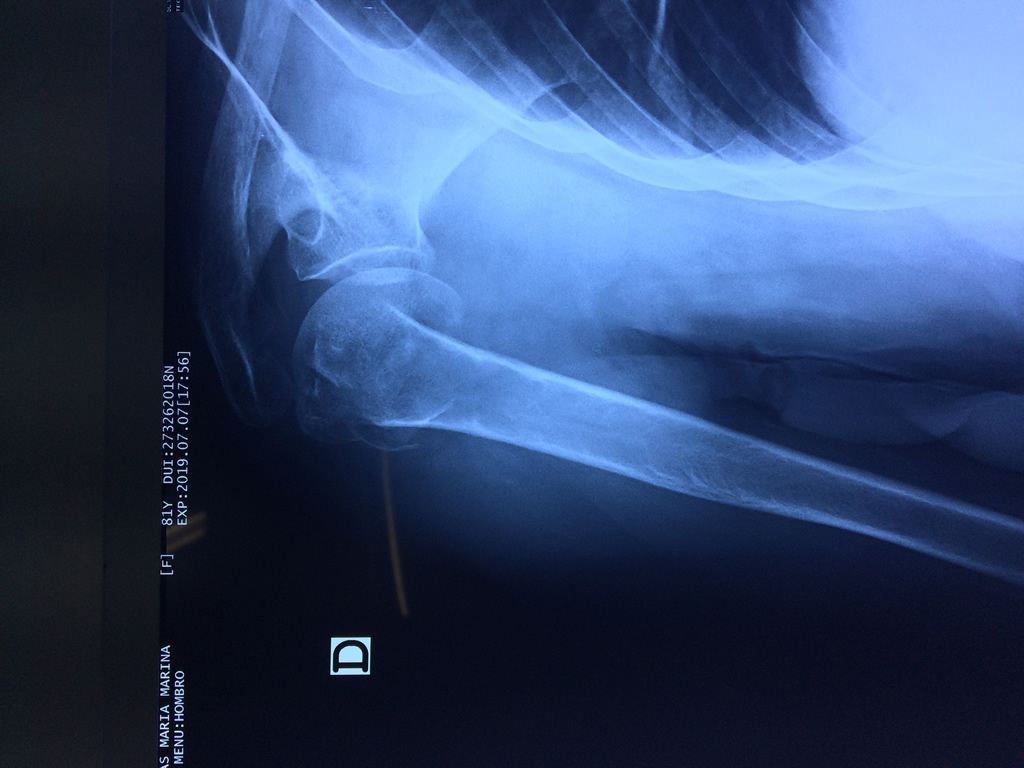

La principal articulación del hombro es la que une la cabeza del húmero con la escápula, recibe el nombre de articulación escapulohumeral y presenta dos superficies articulares, una de ellas corresponde a la cabeza del humero que tiene forma semiesférica y la otra es la cavidad glenoidea de la escápula, estas superficies están recubiertos por cartílago que permiten un movimiento suave e indoloro.

Exteriormente una envoltura de tejido blando circunda el conjunto, es la llamada cápsula articular que está reforzada por varios ligamentos que le dan estabilidad e impiden que los huesos se desplacen más allá de sus límites fisiológicos. Un conjunto de músculos y sus tendones se unen a las superficies de los huesos y hacen posible la movilidad de la articulación, entre ellos es muy importante el manguito rotador formado por cuatro músculos que proporcionan movilidad y estabilidad al hombro.

Varias estructuras transparentes en forma de saco llamadas bolsas serosas, permiten el deslizamiento suave de los diferentes componentes móviles. El hombro es la articulación con mayor amplitud de movimientos del cuerpo humano.